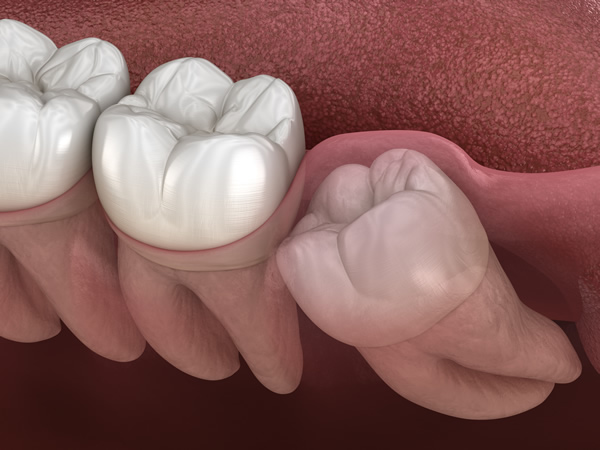

水平埋伏歯の治療について

水平埋伏歯とは、歯茎の中で横向きに生えてしまった歯のことです。これにより、手前の歯を圧迫して痛みや歯並びの乱れを引き起こし、さらに虫歯歯周病の原因にもなります。

このような歯は骨や神経に近い位置にあるため、抜歯には高度な技術が求められます。当院では、精密な診断と高い技術力で、難しいケースの抜歯にも対応しています。他院で治療を断られた場合も、安心してご相談ください。